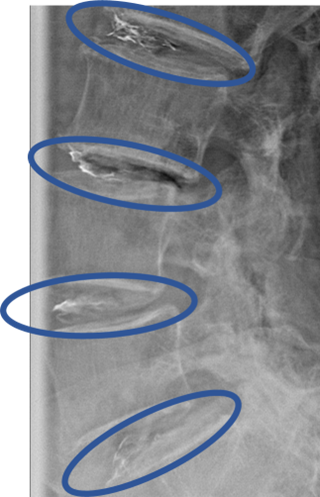

画像及び所見について

L1/2: 椎間板変性、椎間板膨隆

L2/3: 椎間板変性、椎間板膨隆、両側椎間孔狭窄

L3/4: 椎間板変性、椎間板ヘルニア、両側椎間孔狭窄

L4/5: 椎間板変性、椎間板ヘルニア

L5/S: 椎間板変性、椎間板膨隆、両側椎間孔狭窄

以上の事が画像上認められます。

L2/3、3/4、4/5、5/Sに

椎間板変性、椎間板ヘルニア、両側椎間孔狭窄を認め、主症状の原因の可能性が高い。

DiscoGelを入れた後の画像になります。